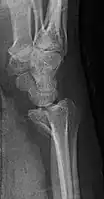

-

Lateral projectional radiograph of the same fracture -